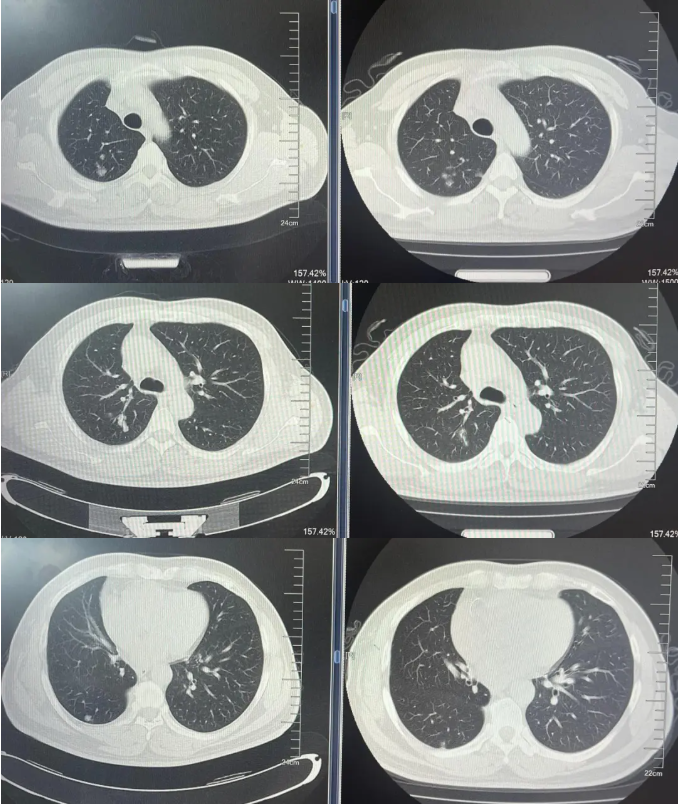

病例1:患者男,68岁。2024年6月以“胸闷气短1个月”为主诉于当地医院检查治疗。查CT提示左肺下叶肿物,纵隔、双肺门多发肿大淋巴结,左侧胸腔积液,左侧胸膜增厚。于当地医院行胸水穿刺引流查癌细胞提示肺腺癌。临床分期:cT2aN3M1a IVA期。患者于当地医院行血液基因检测未见敏感突变,使用AP方案化疗后病情进展。2025-1入我院后行肺穿刺活检,病例提示腺癌。行基因检测提示:ERBB2突变(丰度3.5%)。行德曲妥珠单抗(T-DXd)治疗至今。最佳疗效PR,目前持续有效中,PFS已超过7个月。患者使用德曲妥珠单抗期间出现II级恶心呕吐,经对症治疗可缓解。

德曲妥珠单抗治疗4周期(2025.5)疗效对比

德曲妥珠单抗治疗6周期(2025.7)疗效对比

病例2:患者男,61岁。2023年8月于外院行肺CT提示:右肺下叶肿块。2023年10月23日于我院行单孔胸腔镜下右肺下叶切除术、肺门纵隔淋巴结扩清术。术后病理:腺癌低分化(腺泡型占30%,乳头型占30%,筛状占30%,微乳头占10%)。分期pT4N0M0 IIIA期。术后行基因检测提示HER2+(14%),PD-L1 2%+。术后行AC方案化疗4周期后行阿替利珠单抗维持治疗1年。末次用药时间:2024年11月1日。2025年2月复查肿瘤标志物升高,肺HRCT示:双肺多发结节,考虑转移。行血液基因检测提示:ERBB2 35.5%突变,CDK1 9.5%突变,MDM2 4.92%突变。患者DFS 14m,阿替利珠单抗停药后3个月出现复发转移,可见传统免疫治疗效果不佳。恰逢德曲妥珠单抗一线新尝试DESTINY-lung 04研究公布了入组标准和治疗方案,且该患在术后的组织基因检测和复发后的血液基因检测中都明确存在HER2突变,故行德曲妥珠单抗一线治疗。最佳疗效PR,目前治疗持续有效,PFS超过6个月。无药物相关不良反应发生。

德曲妥珠单抗治疗4周期(2025.4)疗效对比